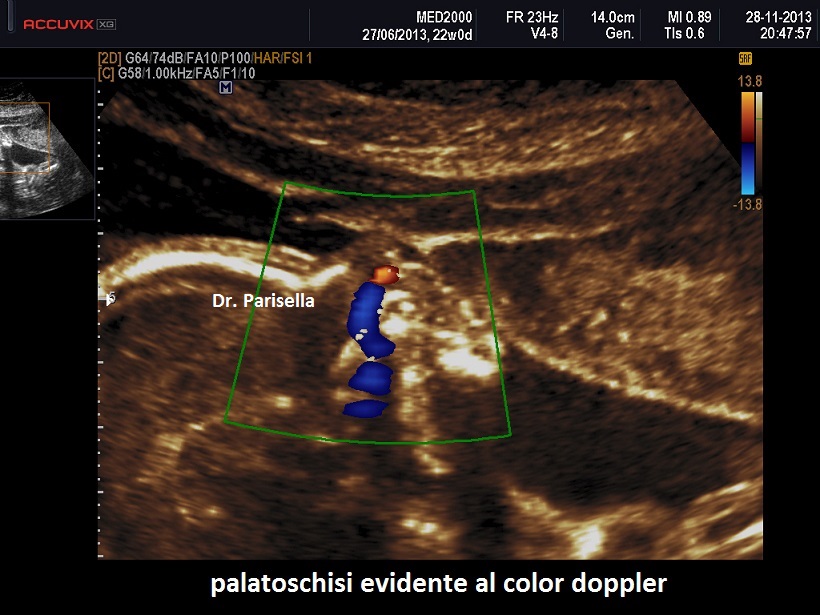

palatoschisi